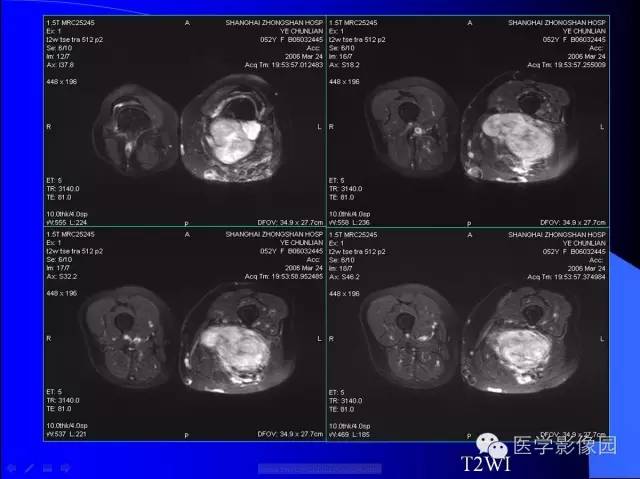

【病例】大腿恶性孤立性纤维瘤1例MR

病史:女,52岁,左大腿包块30年,逐渐长大。

孤立性纤维瘤起源于弥漫分布于人体结缔组织中CD34阳性的树突状间叶细胞。多见于头颈部、上呼吸道、腹腔和周围软组织。发病高峰40~ 60 岁, 女性多见。临床上多数病例表现为局部缓慢生长的无痛性包块。随着包块的增大, 会出现相应部位的压迫症状。孤立性纤维瘤多数病例临床上呈良性经过, 约10% 的非典型性和恶性孤立性纤维瘤局部复发率或远处转移率较高(80% )。